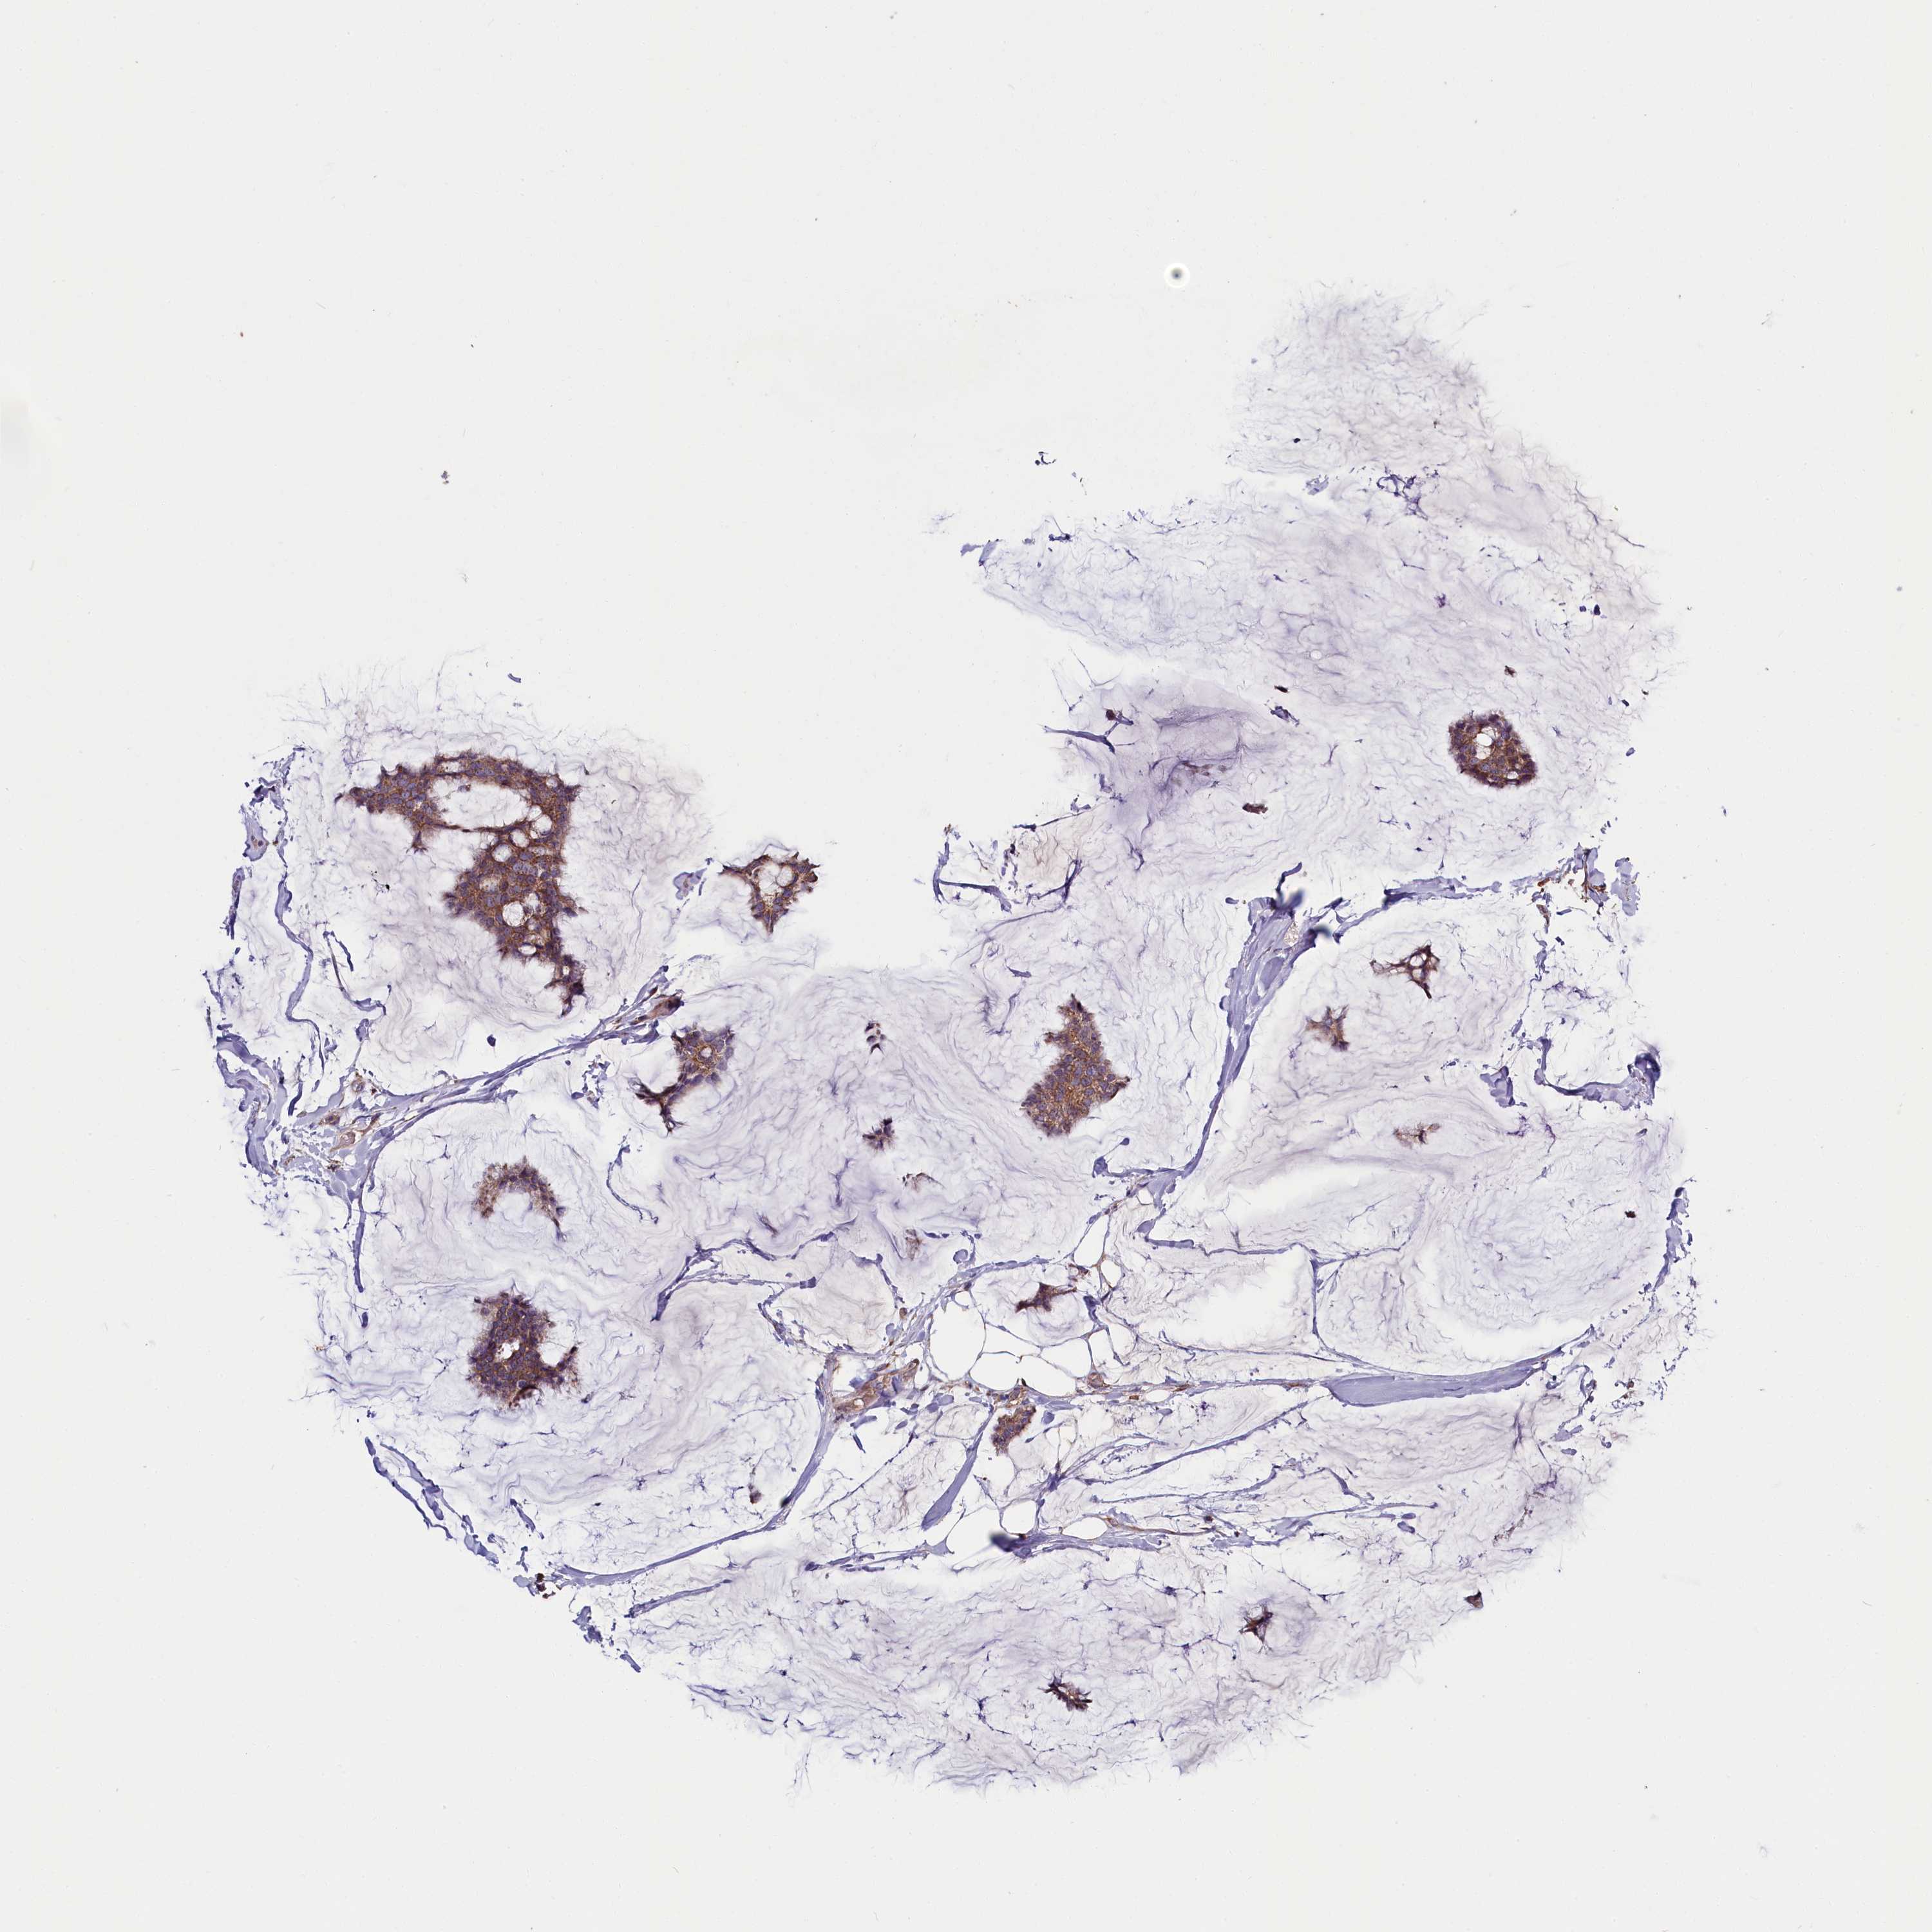

BRCA TCGA BRCA VALIDATION PROTEIN EXPRESSION

ANTIBODIES

AND

VALIDATION